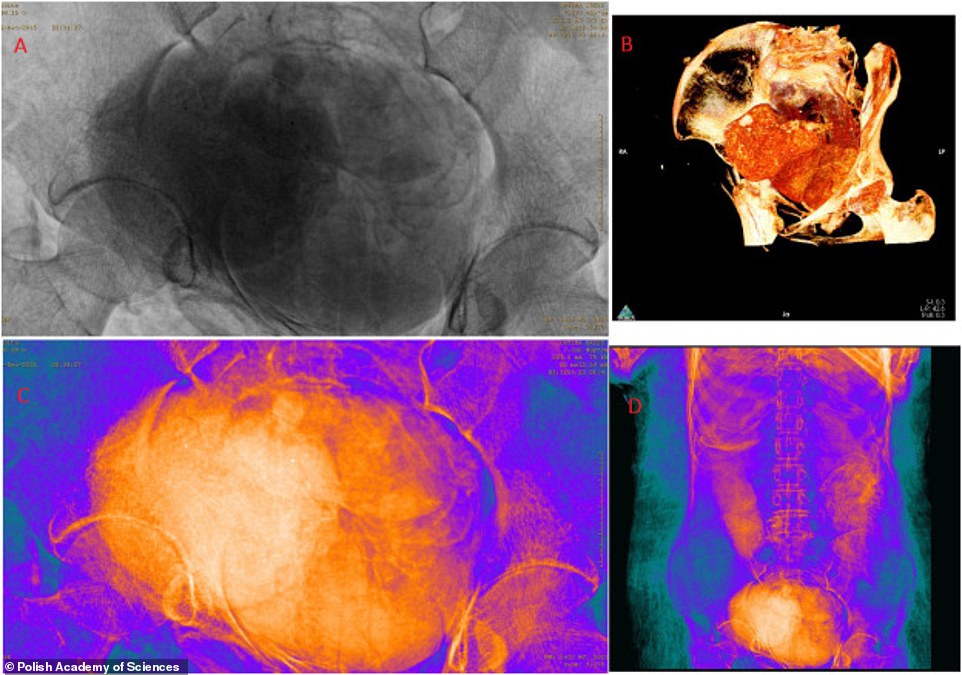

Ученые использовали множество различных фильтров, чтобы изучить мумию сканером, не дотрагиваясь до нее. Было установлено, что женщина находилась примерно на 26-28 неделе беременности, плод находится в положении эмбриона, пол ребенка определить не удалось.